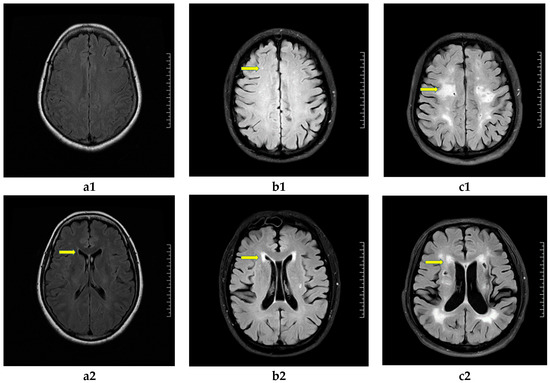

2.2.3. Evaluation of Cranial MRI